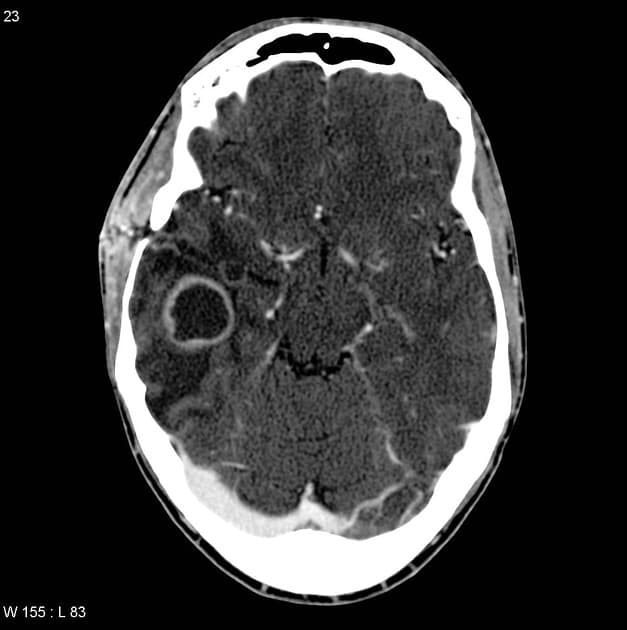

- Cộng hưởng từ (MRI) phát hiện một khối trong trục (intra-axial) lớn, tín hiệu không đồng nhất (heterogeneous signal) ở vùng thùy đỉnh - thái dương trái.

- Khối này gây hiệu ứng chiếm thể tích đáng kể, dẫn đến lệch đường giữa (midline shift), chèn ép sừng chẩm của não thất bên trái (left lateral ventricle occipital horn) và được bao quanh bởi phù vận mạch (vasogenic edema).

- Tổn thương cho thấy các vùng hạn chế khuếch tán (diffusion restriction) và tăng quang không đồng nhất (heterogenous post-contrast enhancement) sau tiêm thuốc cản quang.

- Đặc điểm trên MRI phù hợp nhất với một khối u thần kinh đệm nguyên phát độ cao (WHO độ IV).

- Sinh thiết xác nhận đây là u nguyên bào thần kinh đệm đa hình (glioblastoma multiforme), IDH dạng hoang dại (wild type), WHO độ IV.

- "Cộng hưởng từ cho thấy các đặc điểm điển hình như tăng quang không đồng nhất, hoại tử trung tâm, hạn chế khuếch tán và phù vận mạch lan tỏa kèm hiệu ứng chiếm thể tích."

U nguyên bào thần kinh đệm IDH dạng hoang dại (WHO độ IV) là khối u ác tính nguyên phát phổ biến và nguy hiểm nhất ở não người lớn. Bệnh thường khởi phát nhanh với các triệu chứng như động kinh, suy giảm thần kinh hoặc liệt nửa người. Trên cộng hưởng từ, khối u hiện diện như một khối trong trục lớn, tín hiệu không đồng nhất, tăng quang dạng vòng không đều, hoại tử trung tâm và phù vận mạch lan rộng xung quanh. Hạn chế khuếch tán cho thấy mật độ tế bào cao. Lệch đường giữa và chèn ép não thất phản ánh hiệu ứng chiếm thể tích rõ rệt. Chẩn đoán xác định cần sinh thiết mô và phân tích phân tử: tế bào khối u dương tính với các dấu ấn thần kinh đệm (GFAP, Olig2), và xét nghiệm IDH1 âm tính trong dạng hoang dại. Khác với các u thần kinh đệm có đột biến IDH, ung thư dạng hoang dại thường gặp ở người lớn tuổi hơn và tiên lượng xấu hơn nhiều. Các chẩn đoán phân biệt bao gồm u di căn, ung thư hạch và u sao bào ác tính, nhưng hình ảnh học và miễn dịch mô hóa học giúp phân biệt rõ ràng.